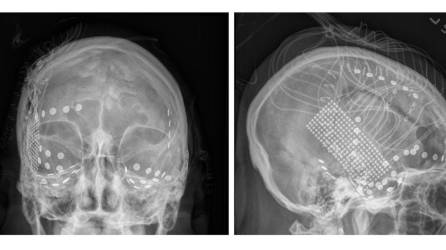

Britney Spears revela que sufre daño cerebral

La cantante reveló en Instagram que sufre daño cerebral. Su confesión reaviva el debate sobre su salud y privacidad.